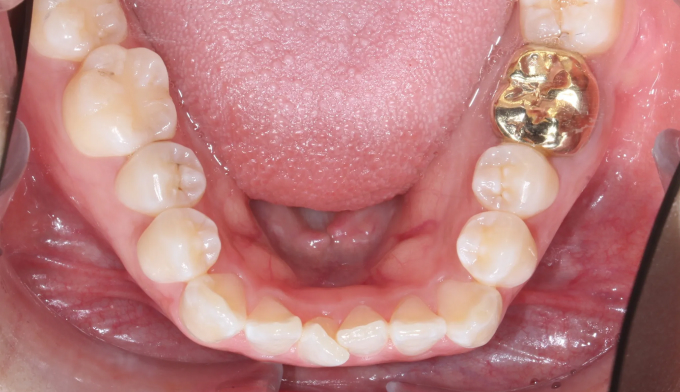

미니스크류를 이용하여 어금니 교합을 변화시켜 개방교합을 해소하였습니다. 이와 동시에 어금니의 후상방 이동으로 앞니 배열공간을 만들었고 앞니를 가지런하게 배열시킬 수 있었습니다.

치아교정이 진행되면서 구강위생관리가 좋지않아 잇몸 염증과 초기 충치가 다수 관찰되었습니다.

총 치료기간은 15개월 소요되었습니다.